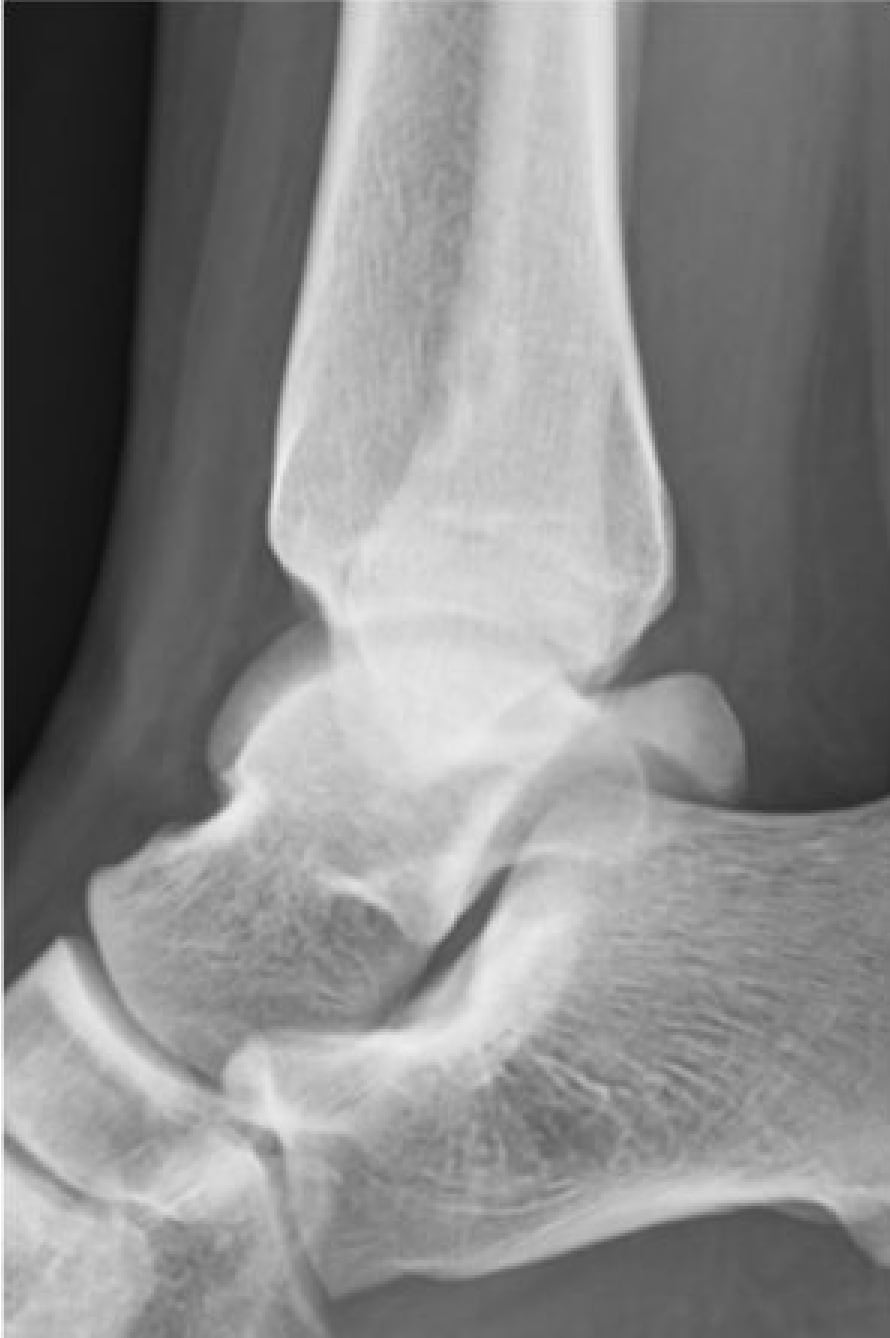

2020-12-09 スポーツ整形 ページ内リンク 後方インピンジメント症候群(三角骨障害)【スポーツ整形外科】 後方インピンジメント症候群(三角骨障害)【スポーツ整形外科】 サッカーやラグビーのキック動作やクラシックバレエのポアント肢位で足関節後方の骨が衝突して疼痛が発生する。⇒鏡視下切除により症状消失。 術前 術後 関連ページ スポーツ整形 一覧へ戻る